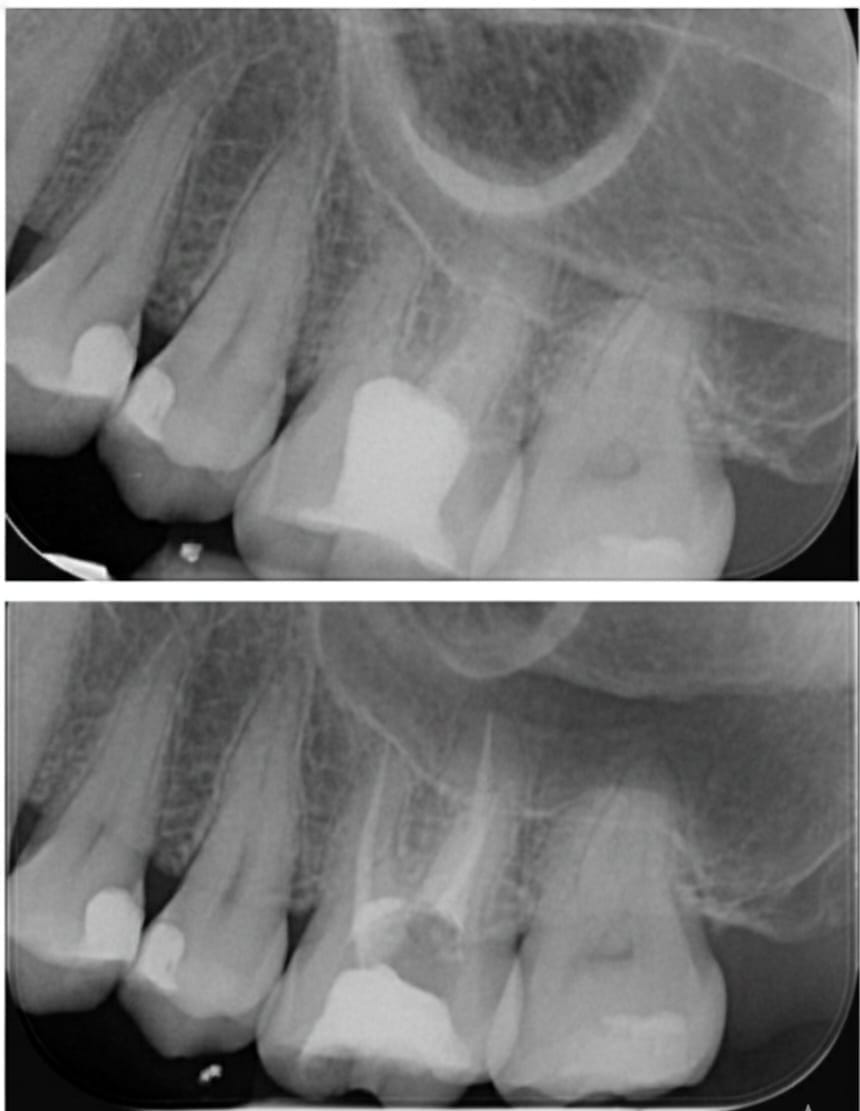

Folosind microscop endodontic, tehnologie digitală și instrumente rotative moderne, asigurăm curățarea perfectă a canalelor radiculare și o vindecare rapidă, fără disconfort.

Microscop endodontic pentru precizie totală

Fiecare canal este tratat sub mărire de până la 25x, pentru curățare completă și rezultate durabile. Utilizarea microscopului reduce semnificativ riscul apariției infecțiilor recurente

Permite vizualizarea detaliată a canalelor dentare și tratarea completă a celor mai fine ramificații. Fără complicații, fără infecții ascunse.

Consultația și radiografia digitală

Se realizează o radiografie pentru a evalua structura dintelui și extinderea infecției. Stabilim planul exact de tratament.